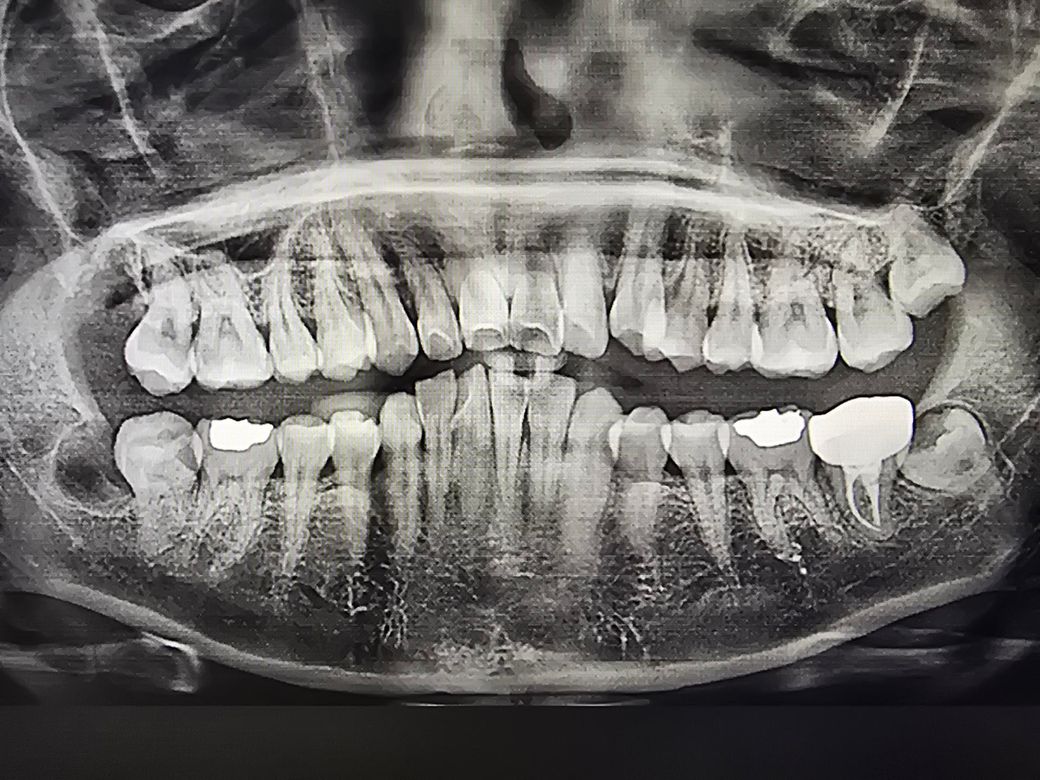

사랑니 발치 후 염증 치료 중 개구장애와 흡연여부 문의

사랑니 발치 한지 10일차인데도 불구하고 염증으로 인해 항생제먹고있습니다.

• 1번 째 사진